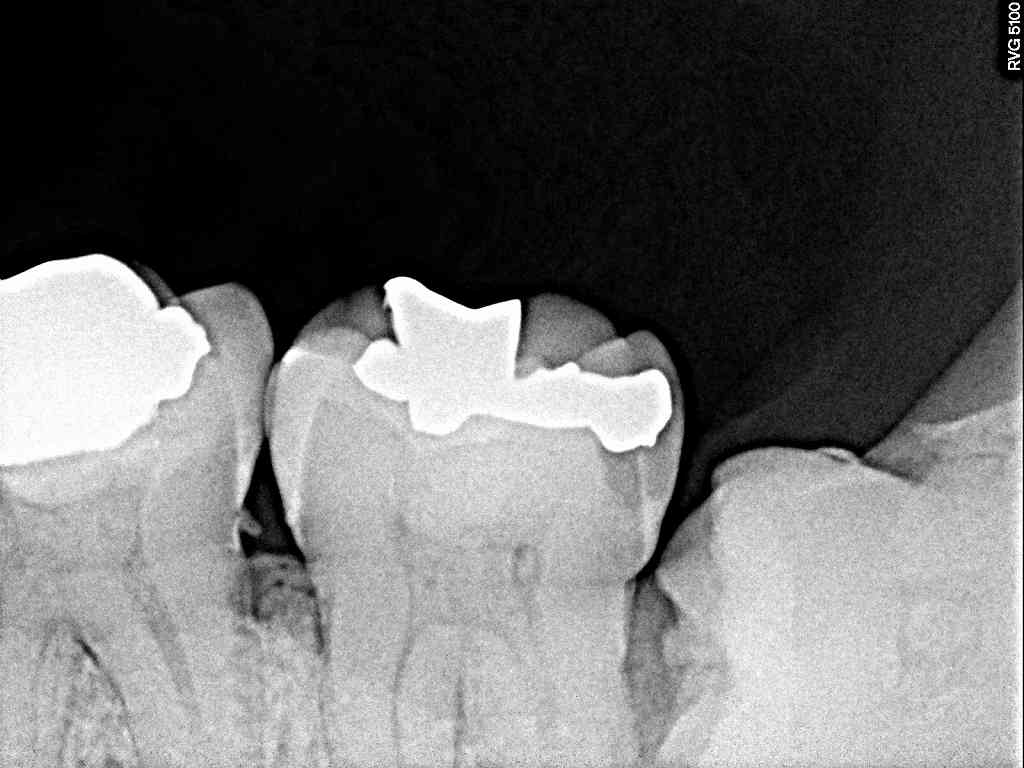

側面から見てもわずかに穴が開いているところから

親不知が見えてきていました

デンタルではあまりよく見えません

大きな歯が横たわっていました